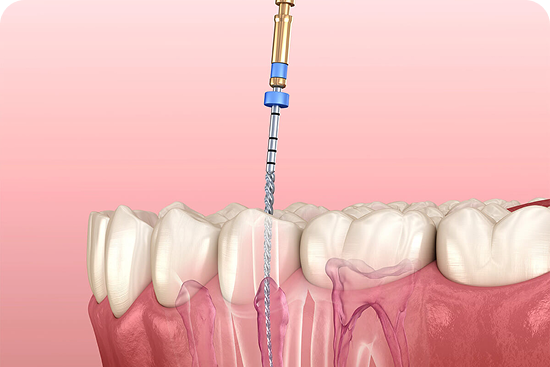

STEP 01

Removal of Infection

We gently access the tooth and remove all damaged and infected pulp tissue using precise microscopic tools to ensure total elimination of decay.

STEP 02

Cleaning & Shaping

The empty root canals are meticulously disinfected and shaped using advanced endodontic technology to prepare them for a secure, airtight filling.